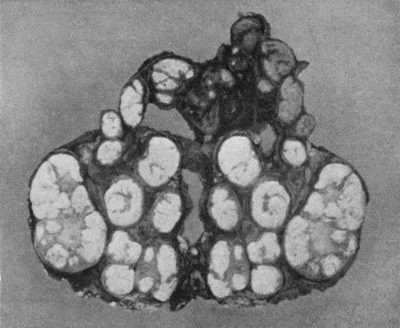

209 59.Dermoid Cyst of Ovary

213 60.Carpal Ganglion in a woman æt. 25